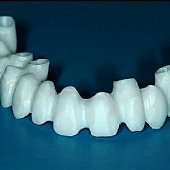

• Fertig gefrästes und gebackenes Zirkonoxyd-Gerüst zum Aufbrennen der Keramik.

• Fertige Vollkeramikbrücke.

• Detailansicht der fertigen Vollkeramikbrücke.